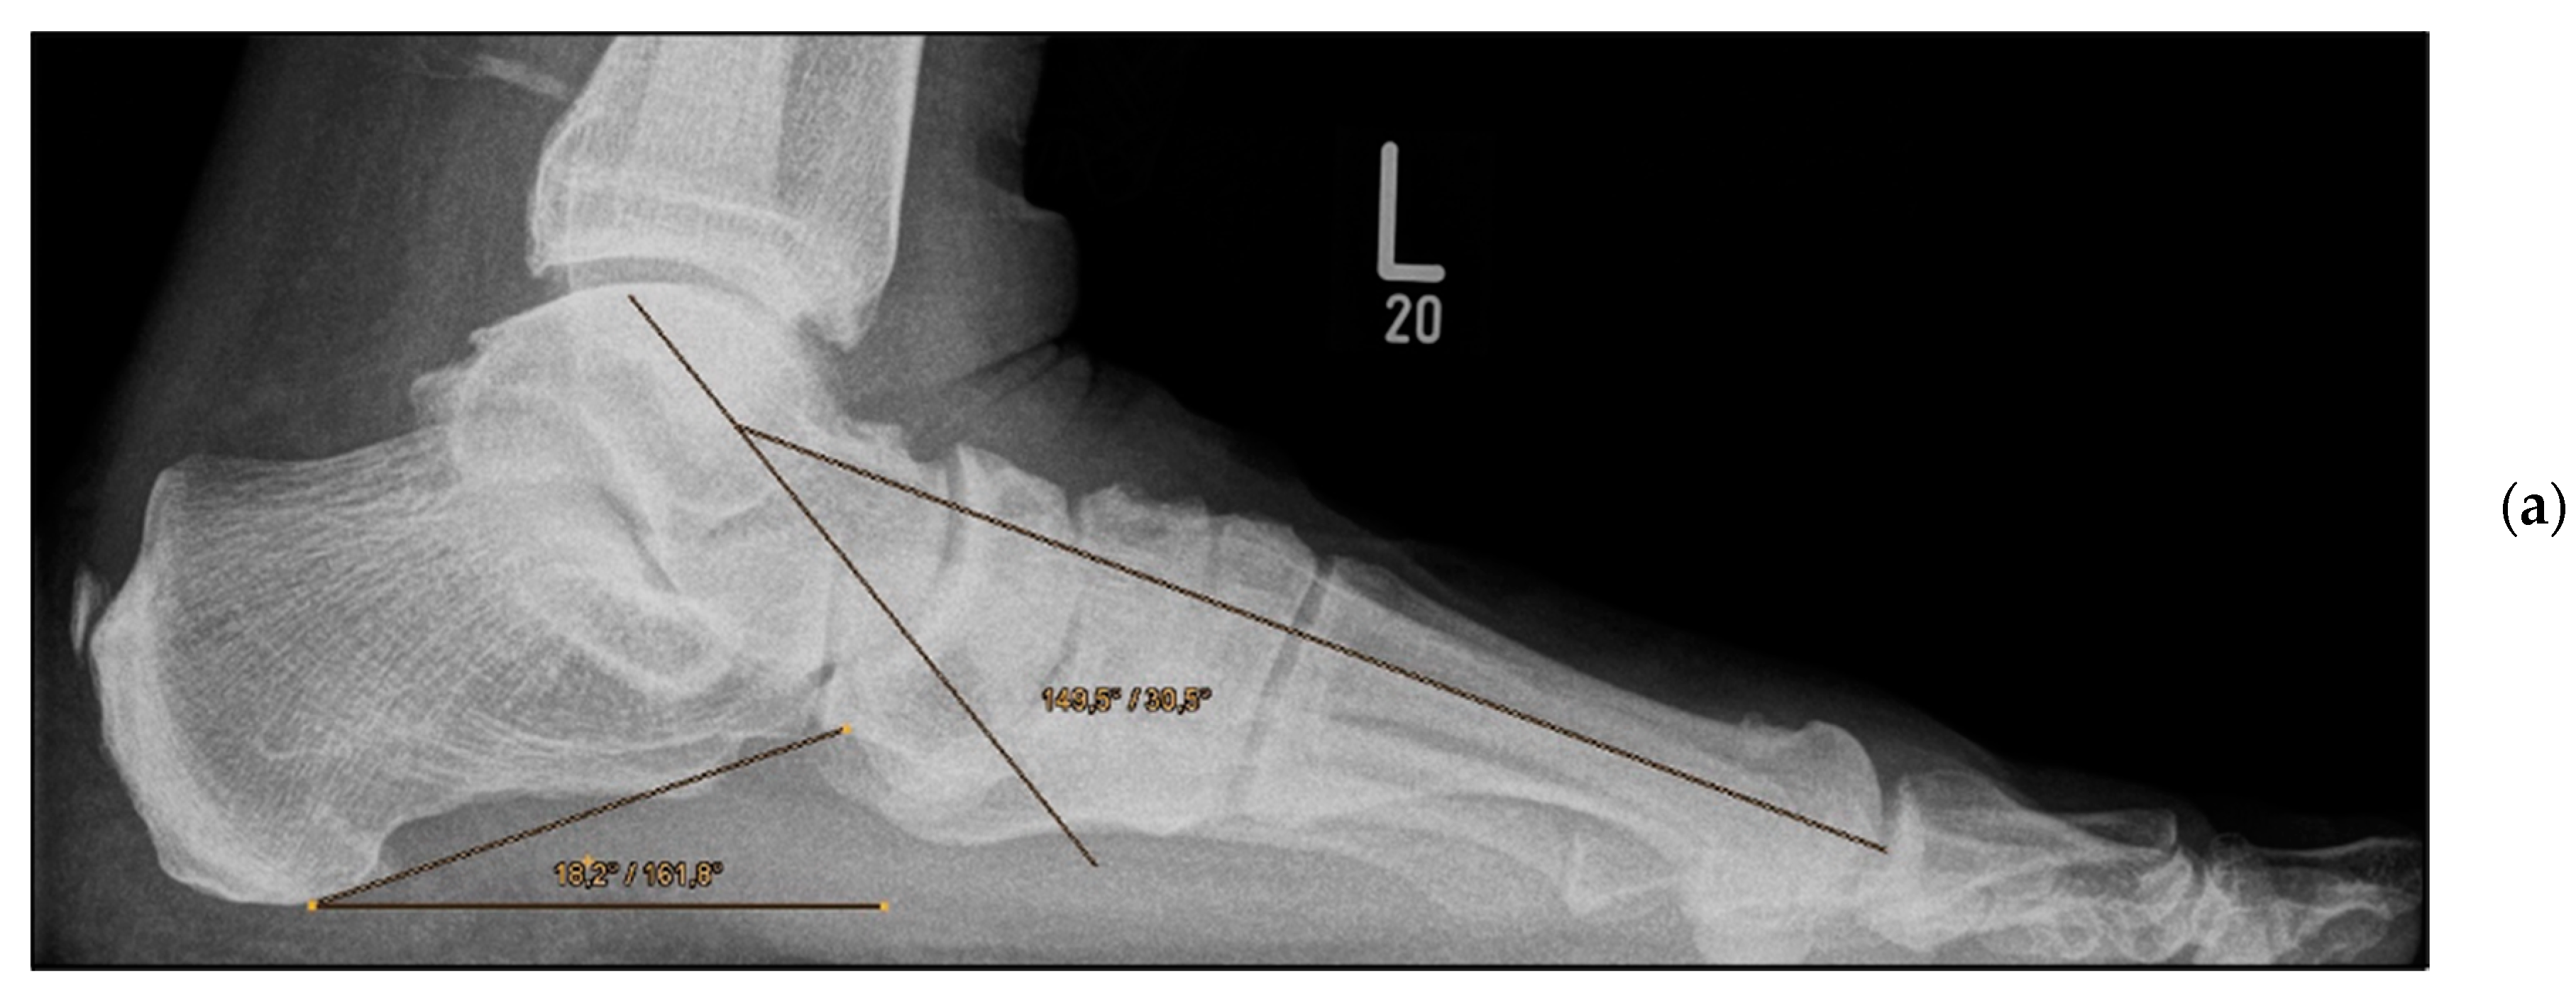

Figure 5.

Pre- and post-operative radiographic findings of double arthrodesis, left foot. (a) Lateral view pre-operative, (b) lateral view post-operative after implant removal.

Double Arthrodesis (Group B). Firstly, subtalar arthrodesis was performed via a lateral subtalar approach. Care was taken to ensure thorough resection of the articular surfaces and extensive release to achieve adequate correction of the valgus deformity and avoid the development of pseudarthrosis. Here, too, the insertion of autologous cancellous bone was considered obligatory. Fixation was achieved by means of two percutaneously inserted lag screws (diameter of 6.5 mm). The subsequent talonavicular arthrodesis was performed as previously described (Figure 4a,b and Figure 5a,b).